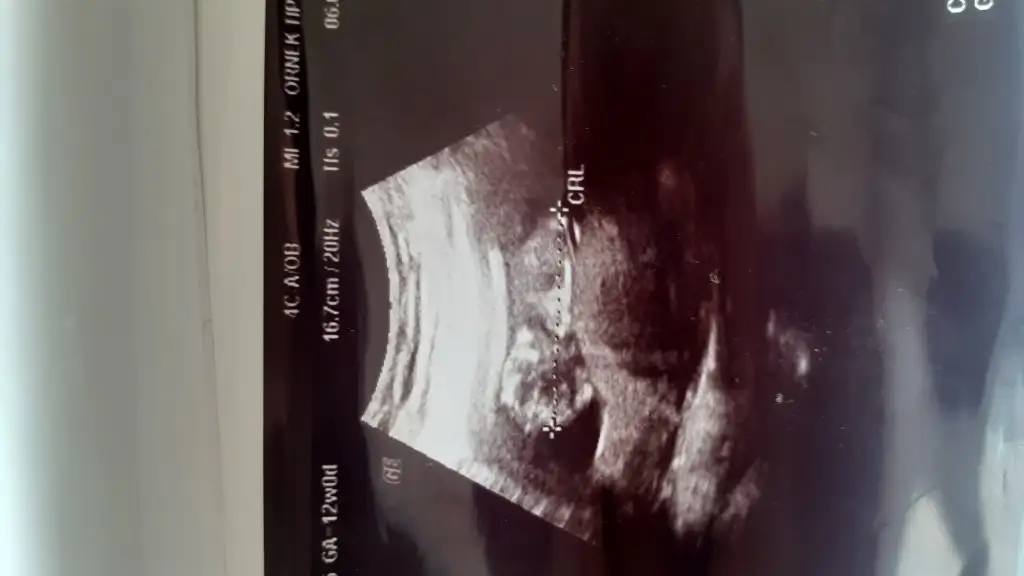

Kızlar bı arkadaş keseye göre tahmin yapıyor ve hep tutuyormuş iki oğlunu da bu şekilde cok yeniyken bile tahmin etmiş...ogullarinda kesesi hep uzunmuş muz gibi...yuvarlak ve yuvarlağa yakın olanlar hep kızdır diyor..ve bayağı emin konusuyor..benimki şişman bı fasulye gibi oo kesin kız görürsün dedi...sizlerin keselerinin şekli nasıldı ve cinsiyet neydi konusalimmi 😊

8+1 göre minik kızlar hızlı gelişmiyor erkekler hızlı gelişiyor yani buda tutma olasılıgı var ama ben 11 yada 12 hafta nub tahmini ediyorum 😊